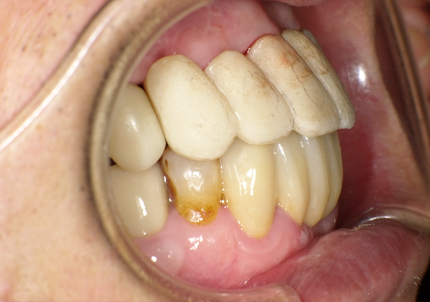

8.補綴物完成(埋入後5か月)

9.左下3本最終補綴装着(2021年11月)

10.口腔内写真(2022年2月)

特に問題無く経過はとても良いです。

患者様ご本人も「良く咬めてとても良い」と満足されています。